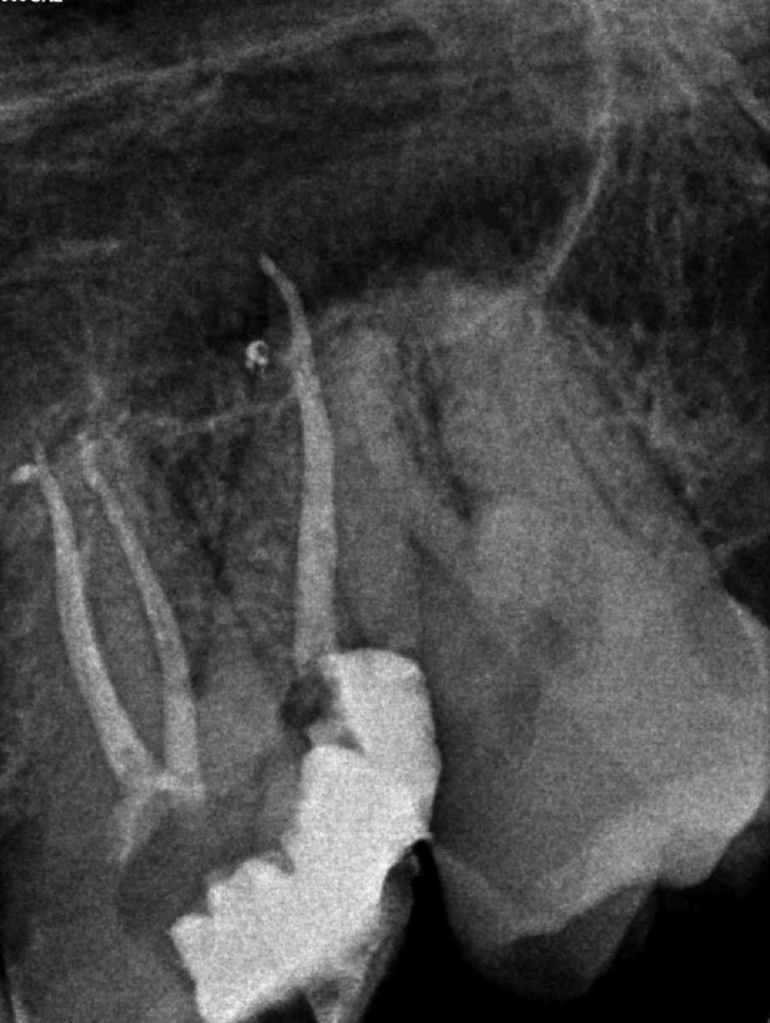

Molar inferior, conducto CM

Molar inferior, conducto MC, Reeco prendo